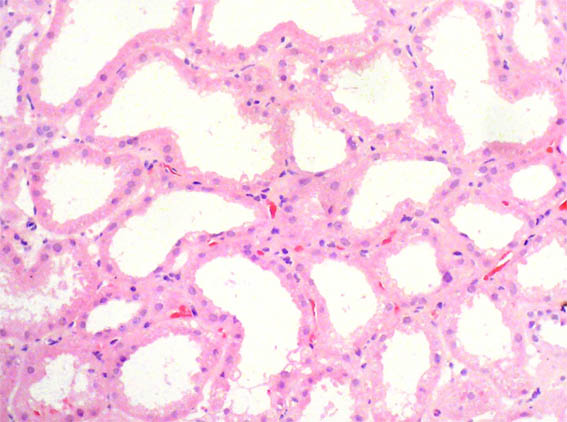

Figure 1. H&E , X200.